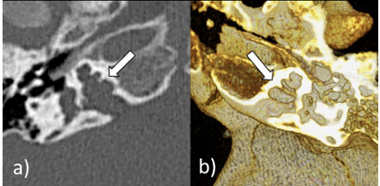

Two half-brothers of a healthy mother were diagnosed with bilateral sensorineural hearing loss. The maternal grandfather was deaf. Exome sequencing revealed a maternally inherited, hemizygous, likely pathogenic variant NM_000307.5:c. 1000A>G, p.(Lys334Glu) in the POU3F4 gene in both brothers. Both brothers received an MRI and CT scan to plan cochlear implantation. MRI showed that the cochlea had a very wide opening to the internal auditory canal on both sides with a corkscrew-like shape. This was confirmed on CT and indicates incomplete partition type III (X-linked deafness). Mutations in the POU3F4 gene lead to non-syndromic, X-linked deafness (MIM #304400). Absence of a cochlear modiolus with a dilated lateral internal auditory canal and a thickened stapes footplate as a pathognomonic radiological pattern of this disease were reported [1]. The radiological findings already point to the genetic cause in these patients.

Figure 1: CT of the older brother at the age of 5 years. It shows bilateral cochlear incomplete partition type III. Both the right (a) and the left (b) cochlea lack the modiolus and the cribriform plate with preserved interscalar septa. This appearance has been referred to as “corkscrew” sign (arrows).